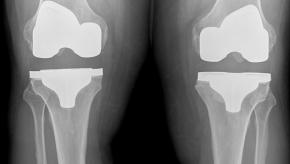

Read ArticleKnee Implant Forecast from 2012 - 2018

The global knee implants market was USD 8.4 billion in 2011, and it's forecasted to reach USD 15 billion in 2018, with compound annual growth rate of 8.64% during 2011 to 2018. The U.S.